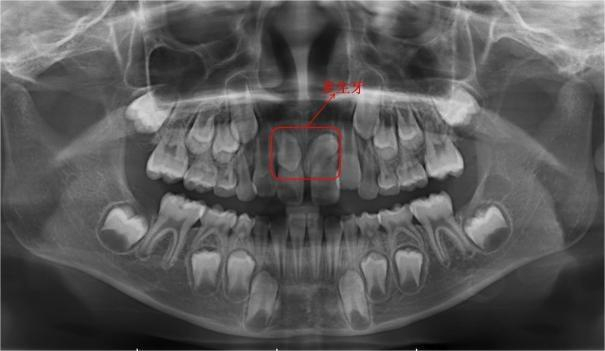

小朋友家长,这是刚拍好的片子,请看这个地方,是因为长了多生牙才影响了正常恒牙的位置,导致两颗牙齿之间的间隙过大。

多生牙已经造成了恒牙的间隙过大,需要拔除。你家小朋友的多生牙倒着长还埋伏在骨头了,拔除难度较大,建议预约口腔外科或者微创拔牙门诊进行拔除。到时候还需要拍个CT确定它的三维位置,和周围牙齿的关系。